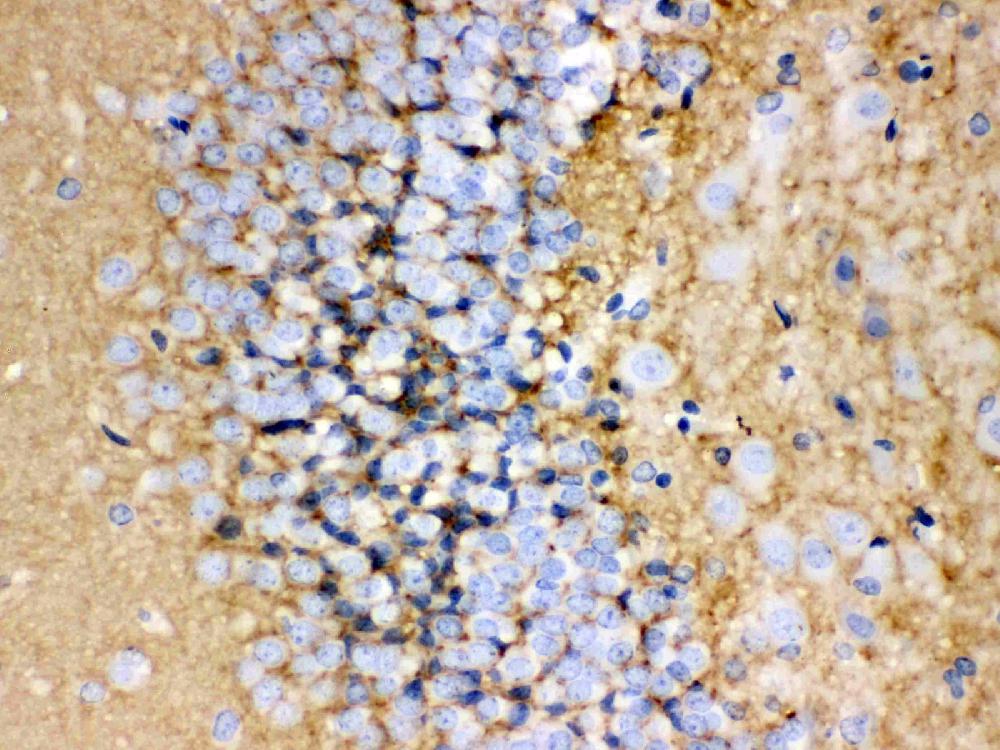

IHC analysis of GAP43 using anti-GAP43 antibody (PA1037).

GAP43 was detected in a paraffin-embedded section of human glioma tissue. The tissue section was incubated with rabbit anti-GAP43 Antibody (PA1037) at a dilution of 1:200 and developed using HRP Conjugated Rabbit IgG Super Vision Assay Kit (Catalog # SV0002) with DAB (Catalog # AR1027) as the chromogen.